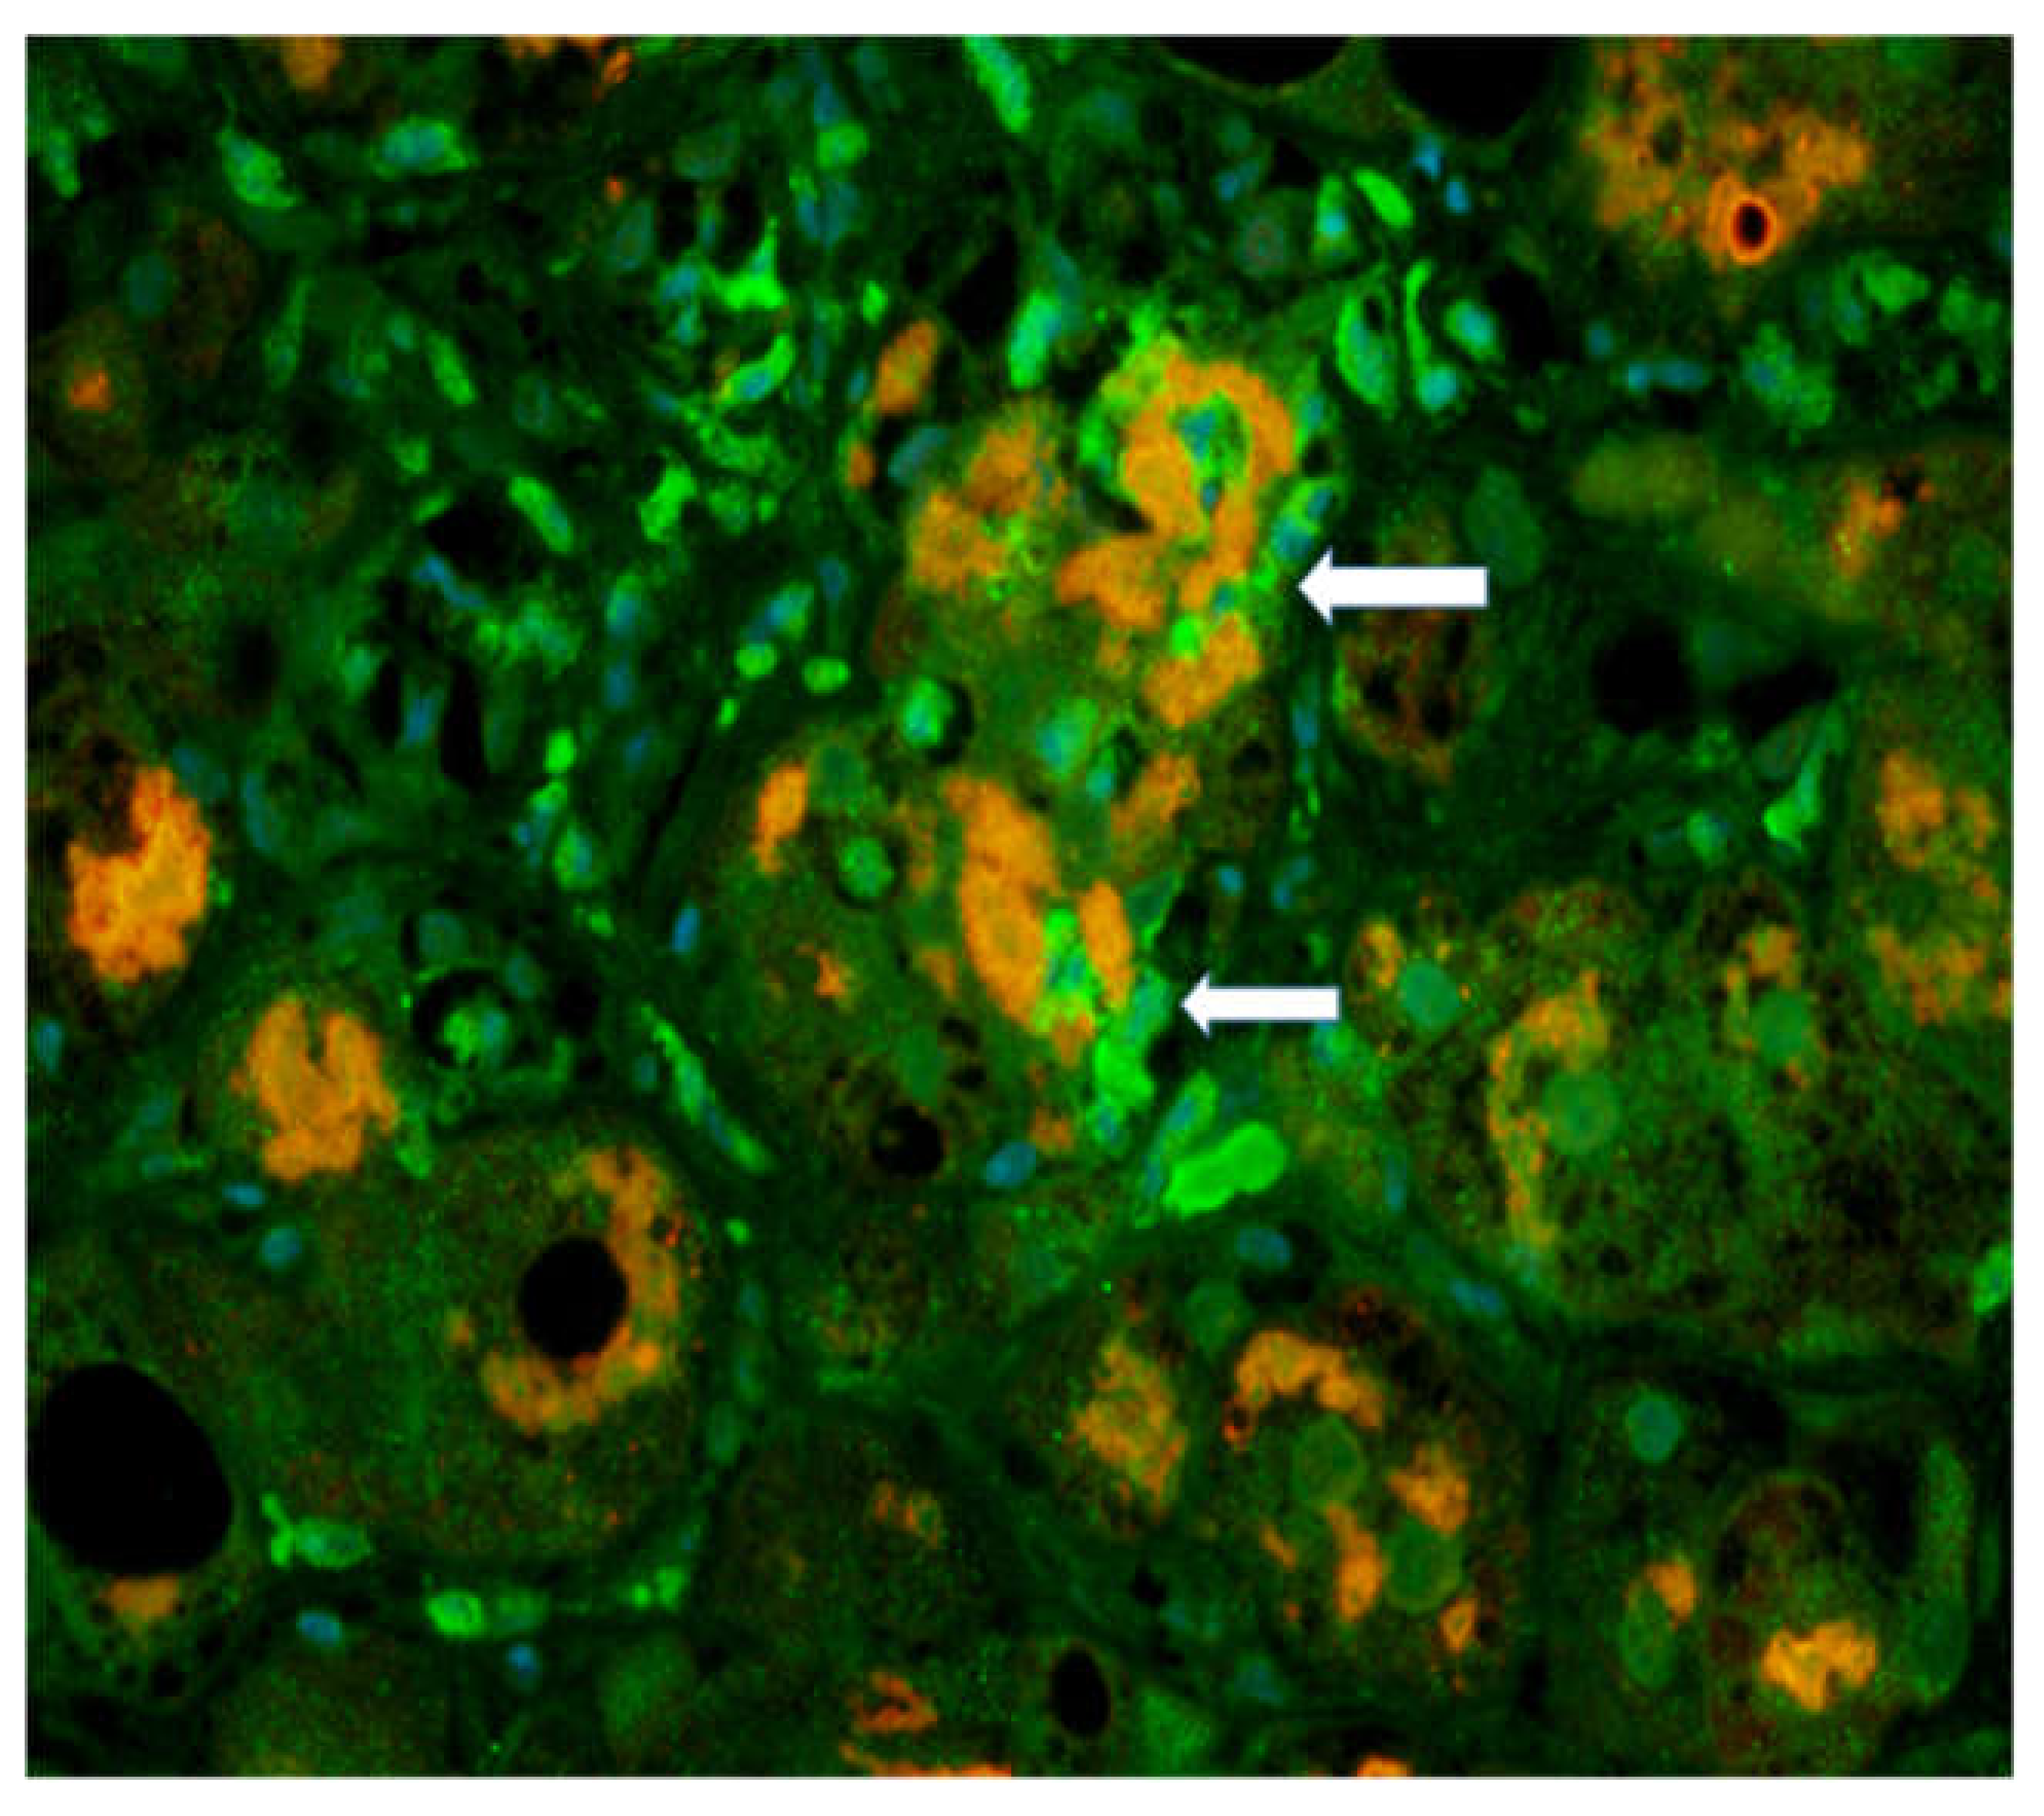

- Afifiyan, N.; Tillman, B.; French, B.A.; Sweeny, O.; Masouminia, M.; Samadzadeh, S.; French, S.W. The role of Tec Kinase signalling pathways in the development of Mallory-Denk bodies in balloon cells in alcoholic hepatitis. Exp. Mol. Pathol. 2017, 103, 191–199. [Google Scholar] [CrossRef]

| 03-027 | 1+ | 0 | 4+ | 4+ | PMN satellitosis | 4+ | 4+ |